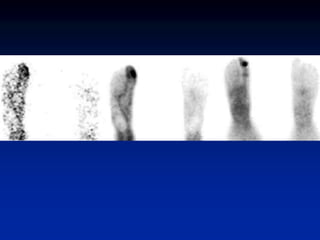

Shin Splints (Periostitis)

• exercise induced pain along medial or

posteromedial aspect of tibia

• associated with increased tracer uptake

• >1/3 of bone length

• middle to distal tibia

• usually bilateral (not necessarily symmetrical)

• microperiosteal tears (via Sharpey’s fibers)

• positive finding does not predict further injury

• Hyperperfusion and hyperemia are

typically present in acute stress fracture.

• Unlike in stress fractures, angiograms and

blood pool images are usually normal in

shin splints. Delayed bone images reveal

longitudinally oriented linear areas of

increased uptake of varying intensity that

involve one-third or more of the posterior

tibial cortex

Shin Splints (Periostitis) •exercise induced pain along medial or posteromedial aspect of tibia • associated with increased tracer uptake • >1/3 of bone length • middle to distal tibia • usually bilateral (not necessarily symmetrical) • microperiosteal tears (via Sharpey’s fibers) • positive finding does not predict further injury

• Hyperperfusion andhyperemia are typically present in acute stress fracture. • Unlike in stress fractures, angiograms and blood pool images are usually normal in shin splints. Delayed bone images reveal longitudinally oriented linear areas of increased uptake of varying intensity that involve one-third or more of the posterior tibial cortex